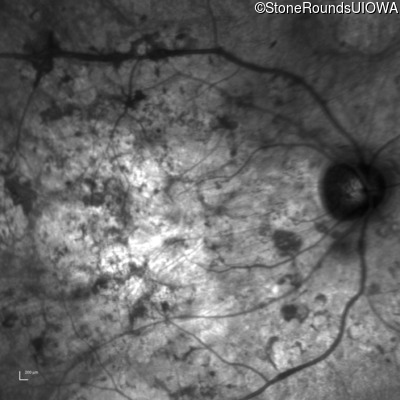

Infrared Fundus Photograph - Right - Hand Motion sc

Exemplar